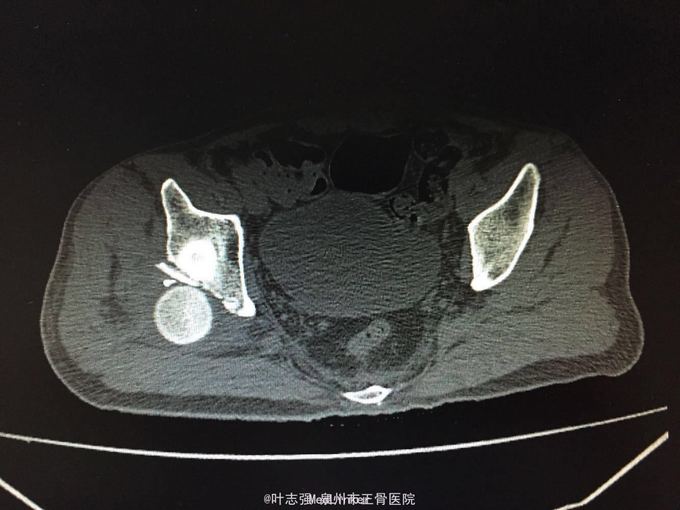

髋臼骨折伴髋关节后脱位ORIF

车祸致左髋部疼痛、活动受限1天。 53岁男性

左髋臼骨折伴髋关节后脱位 行生命支持,股骨髁上骨牵引,

股骨头坏死概率?